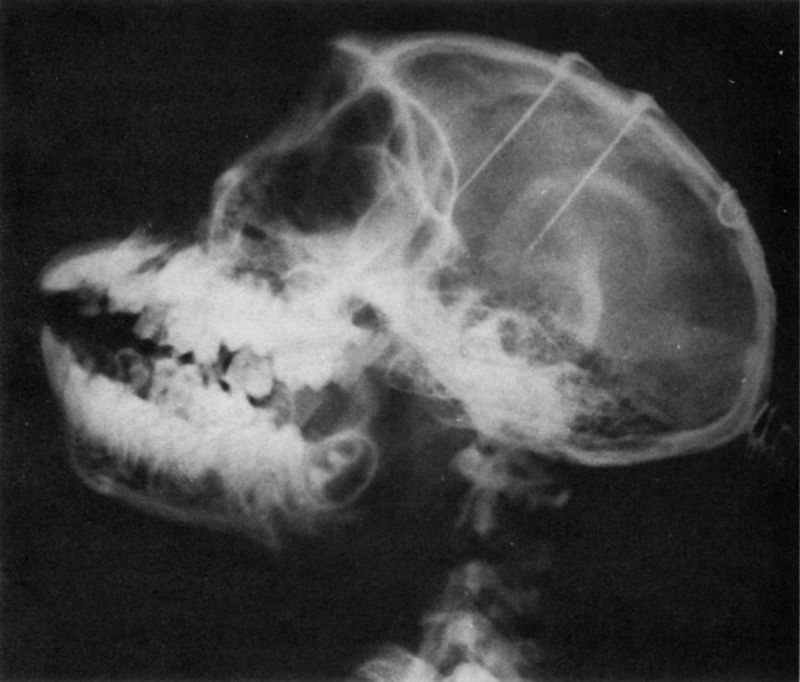

The methodological breakthrough which made it possible to study the brain of behaving animals came in the 1930s when W.R. Hess (106) devised a procedure to implant very fine wires within the brain of anesthetized cats. After the effects of anesthesia had disappeared, the relatively free and normal animal could be electrically stimulated by connecting long leads to the terminals of the implanted electrodes. This procedure was refined in the early 1950s (47, 49) by reducing the size of the electrodes while increasing the number of intracerebral contacts and using aseptic precautions during implantation. Surgical accuracy in reaching chosen cerebral targets was also improved by means of micromanipulators and a precise system of anatomical coordinates which made it possible to reach similar structures in different subjects. Using biologically inert materials such as gold, platinum, or stainless steel wires insulated with teflon allows the electrodes to be left inside of the brain indefinitely. A diagram of the cerebral implantation of one assembly of seven contacts is shown in Figure I and the X ray of the head of a monkey after implantation is seen in Figure 2. Through a small opening in the skull, the shaft is introduced down to a predetermined depth and is secured with dental cement at the point where it passes through the skull. Then the upper portion of the shaft is bent over the bone surface and secured again a short distance away, and the terminal socket is exteriorized on the head. Each contact of the socket corresponds to a determined point in the depth of the brain which is accessible merely by plugging in a connector, a procedure as simple as connecting any electrical appliance to a wall outlet. This technique has been used for ESB in thousands of animals in

As shown in Figure 3, as many as 100 contacts have been implanted in the brain of some chimpanzees without any noticeable neurophysiological or behavioral disturbance, and in several monkeys, contacts have been placed in areas as critical and delicate as the respiratory centers of the medulla without any surgical problems. Electrodes have been used in laboratory animals such as rats, cats, and monkeys, and also in less frequently studied species including crickets, roosters, dolphins, and brave bulls.